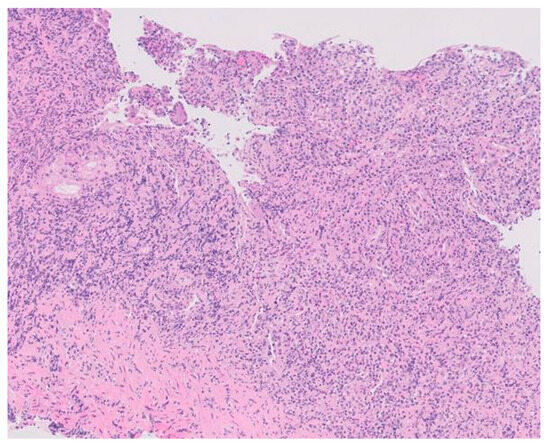

2. Case Description